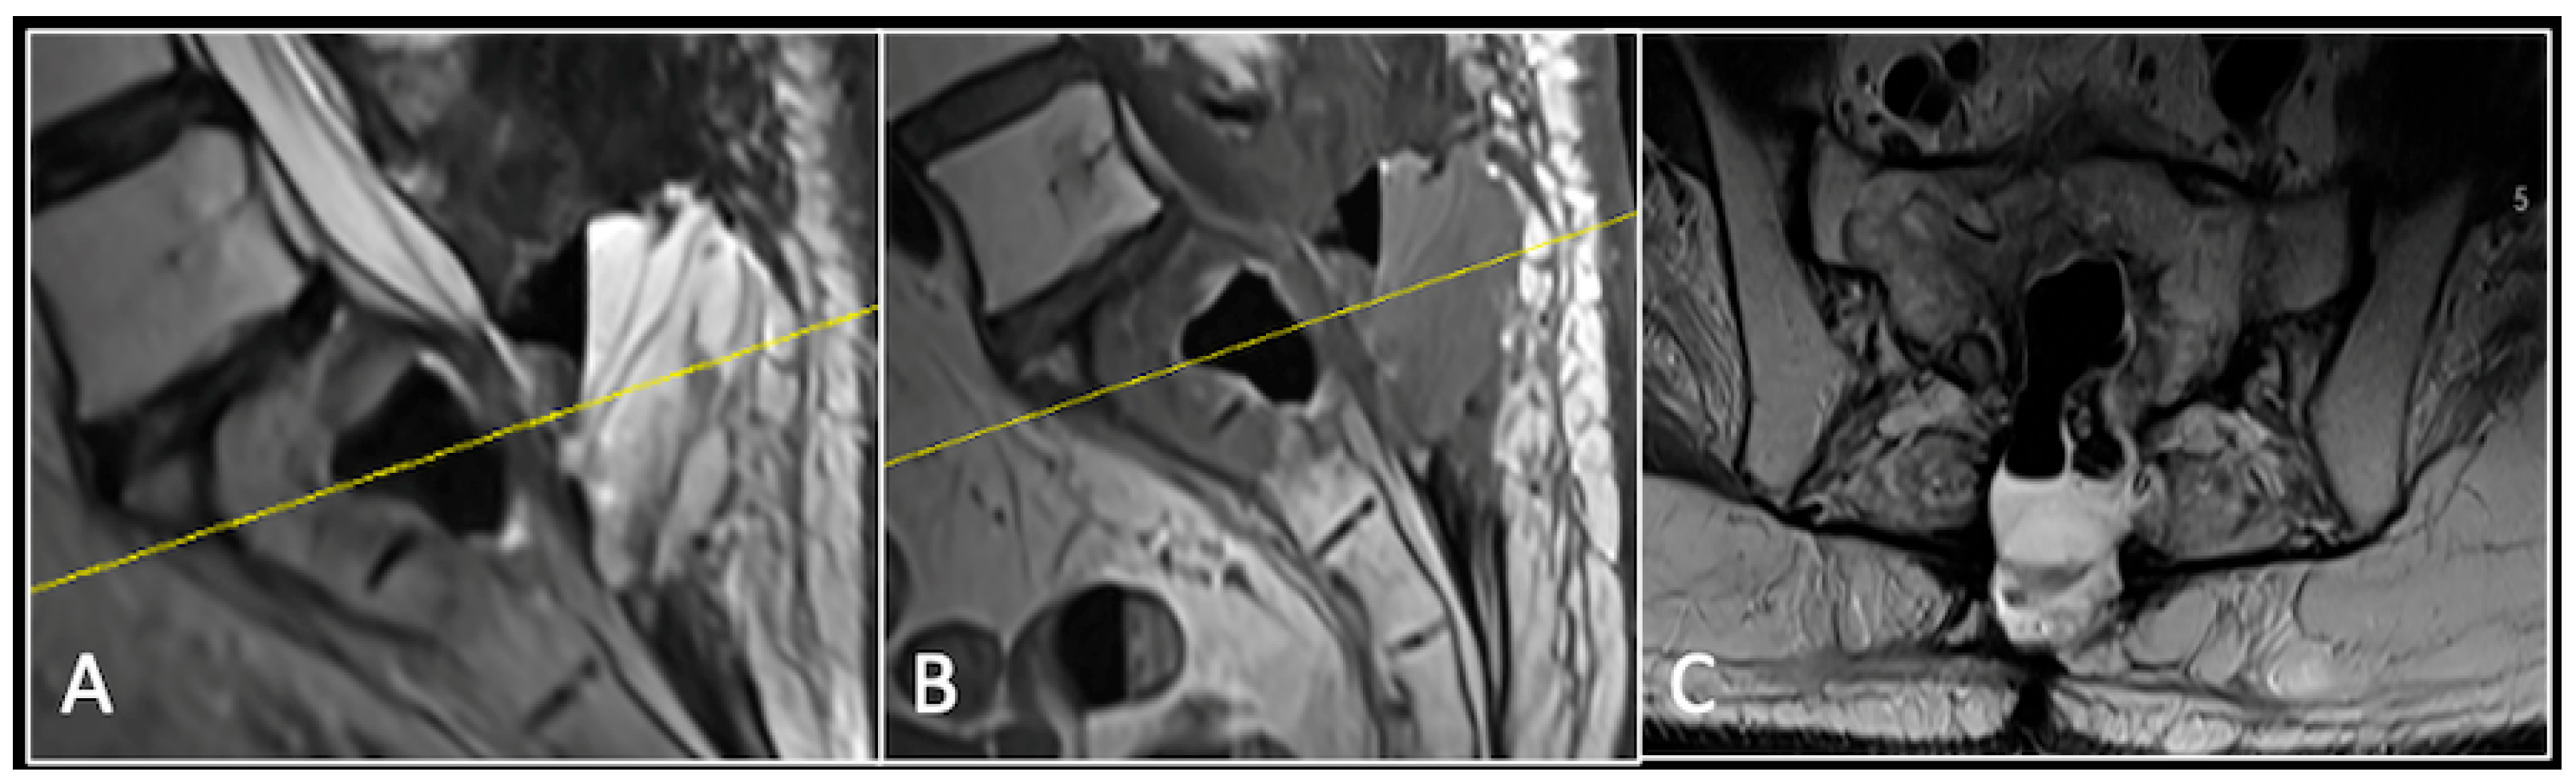

This 63-year-old male presented with sacral pain and right-sided S1 radiculopathy. He was subsequently referred to our institution after diagnostic imaging revealed a destructive lesion within the S1 vertebra (Figure 4). The patient developed symptoms of acute cauda equina syndrome, for which we recommended an emergent surgical decompression to be performed at the referring hospital. Biopsy confirmed a conventional chordoma. The patient chose to undergo separation surgery, given the significant morbidity associated with an en-bloc sacral resection, including sacrifice of the neural structures innervating his bladder and bowel. He received adjuvant proton beam therapy, and 6-monthly surveillance imaging revealed stable disease (Figure 5). Unfortunately, 12 months post-separation surgery, there was evidence of tumour progression with epidural extension and symptomatic deterioration in bladder function, requiring revision surgical debulking (Figure 6).

Figure 4.

MRI demonstrating a destructive lobular sacral mass (arrow) with invasion of the S1 vertebral body and complete compression of the cauda equina neural elements. The yellow line on the axial image represents the plane of the corresponding axial section. (A) T2W sagittal; (B) T1W sagittal; (C) T2W axial.